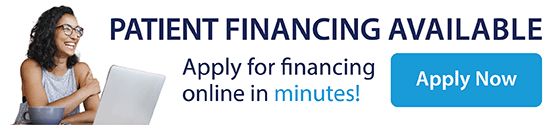

Pocket Reduction Surgery

Pocket reduction surgery is a standard treatment for patients with periodontal disease. This condition causes deterioration of gum tissue and bone along the gumline, resulting in the formation of “pockets” around the teeth. As these pockets become larger, more bacteria get around the teeth and under the gum tissue, leading to further loss of bone and gum tissue until the tooth is lost. If your pockets are too deep to clean with a routine cleaning procedure, you will need a pocket reduction surgery. During the surgery, your dentist will remove the bacteria from the pockets and the tartar from the surface of teeth roots.